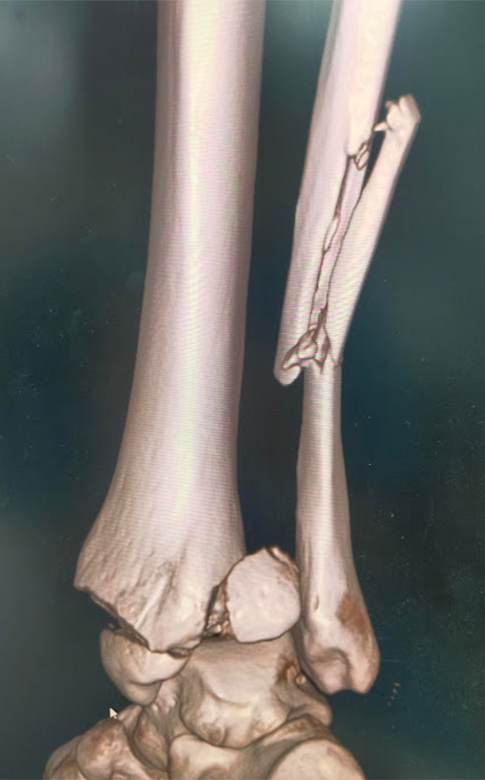

ひざ、股関節を含む、四肢の骨折に対しては、適応があれば手術加療を行い、機能改善および早期の社会復帰を目指しています。

関節を含む骨折は、機能障害を起こしやすく、正確に関節を再建する必要があり、早期リハビリ、機能改善にはとても重要です。

その他、上肢の骨折、足関節や下腿骨などの下肢骨折など、日常的に発生することの多いほとんどの骨折に対する治療に対応しています。

足関節脱臼骨折に対する骨接合術